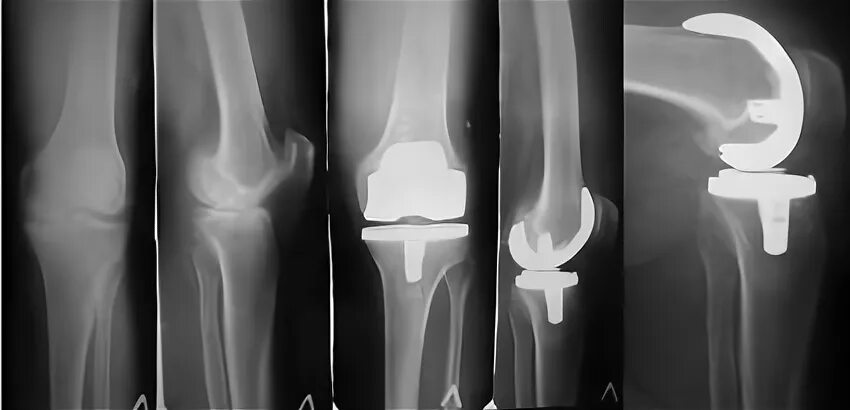

Эндопротезирование коленного сустава чебоксары